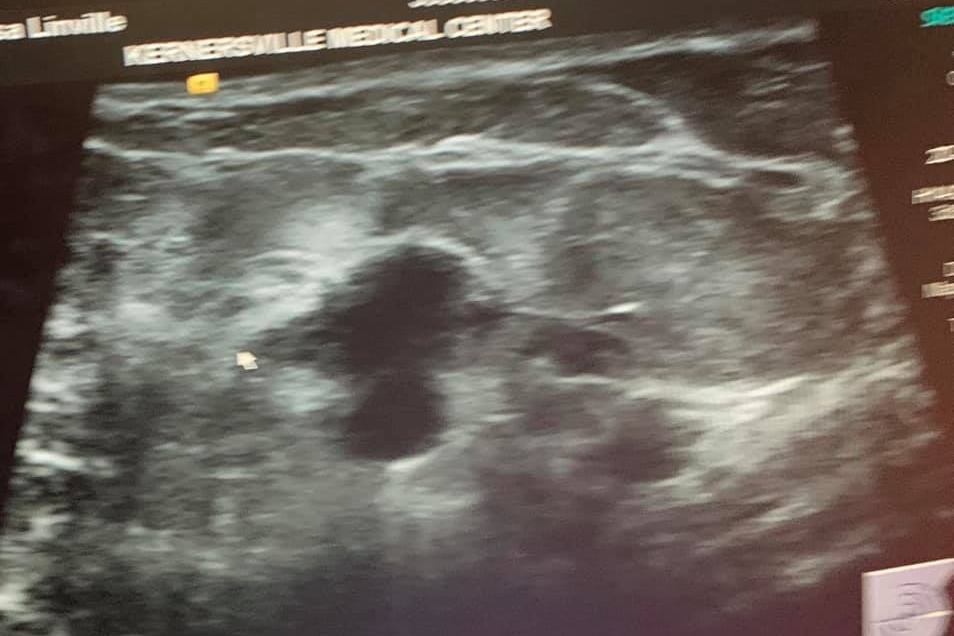

Today, June 18th, just over a month after the attack on Chris, they’ve received the devastating news that Melissa has Stage 2 breast cancer. Grateful for the progression of breast cancer research and treatment, she still faces a long road of chemotherapy and surgery.